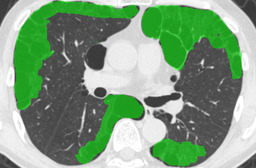

In this paper, we define partial annotation as an annotation format in which only one class is chosen for the annotation and only pixels belonging to the chosen class are annotated per image. For example, in Figure 1(a), although there is ground glass opacity in the image, only consolidation is chosen for annotation and pixels of consolidation are annotated. Partially annotated dataset is less informative for training, however, it is much easier to create compared to fully annotated dataset since annotators only need to focus on one class at a time during the annotation task.

Partially annotated datasets have been utilized previously [8, 9]. In this paper, we propose a new weak supervision technique that fully utilizes partially annotated dataset. Throughout this paper, each DLD pattern is represented or painted in the following colors (CON:cyan, GGO:yellow, HCM:red, EMP:green, NOR:brown.)

Statistics of our dataset are shown in Table 1 and typical images and their annotations for each DLD pattern are shown in Figure 1. In our partially annotated dataset, all the pixels in a slice were manually classified into two classes: dominating DLD pattern and other tissues. In other words, all the pixels in our dataset were assigned one of the labels from either of the two label sets, Lstrong={lCON,lGGO,lHCM,lEMP,lNOR}subscript𝐿𝑠𝑡𝑟𝑜𝑛𝑔subscript𝑙𝐶𝑂𝑁subscript𝑙𝐺𝐺𝑂subscript𝑙𝐻𝐶𝑀subscript𝑙𝐸𝑀𝑃subscript𝑙𝑁𝑂𝑅L_{strong}=\{l_{CON},l_{GGO},l_{HCM},l_{EMP},l_{NOR}\} or Lweak={lCON¯,lGGO¯,lHCM¯,lEMP¯,lNOR¯}subscript𝐿𝑤𝑒𝑎𝑘subscript𝑙¯𝐶𝑂𝑁subscript𝑙¯𝐺𝐺𝑂subscript𝑙¯𝐻𝐶𝑀subscript𝑙¯𝐸𝑀𝑃subscript𝑙¯𝑁𝑂𝑅L_{weak}=\{l_{\overline{CON}},l_{\overline{GGO}},l_{\overline{HCM}},l_{\overline{EMP}},l_{\overline{NOR}}\}. For example, in Figure 1(a), colored pixels were labeled as lCONsubscript𝑙𝐶𝑂𝑁l_{CON} and all the other pixels were labeled as lCON¯subscript𝑙¯𝐶𝑂𝑁l_{\overline{CON}}. In this paper, we call pixels of label lLweak𝑙subscript𝐿𝑤𝑒𝑎𝑘l\in L_{weak} and lLstrong𝑙subscript𝐿𝑠𝑡𝑟𝑜𝑛𝑔l\in L_{strong} as weakly annotated pixels and strongly annotated pixels respectively. Our pixel-wise annotations were created in the following steps. First, up to 3 slices were chosen for the annotation for each HRCT scan and for each slice, one representing DLD pattern was chosen by a radiologist. Second, three radiologists performed pixel-wise binary annotation (e.g. binary annotation between lCONsubscript𝑙𝐶𝑂𝑁l_{CON} or lCON¯subscript𝑙¯𝐶𝑂𝑁l_{\overline{CON}}) for each slice. Finally, the radiologists’ annotations were merged by taking majority classes for each pixel (i.e. pixels labeled as a DLD pattern by more than 2 radiologists became the corresponding DLD pixel). In addition to the DLDs annotation, lung fields were manually segmented under the supervision of radiologists and training and testing were conducted only within the lung fields.

Figure 1: Typical slices for each DLD classes. Slices of HRCT are shown in lung window setting (window-center=-600, window-width=1500) with annotated labels superimposed in transparent colors. Note that even if more than one DLD patterns existed, only one DLD pattern was chosen and annotated for a slice to facilitate the annotation process.